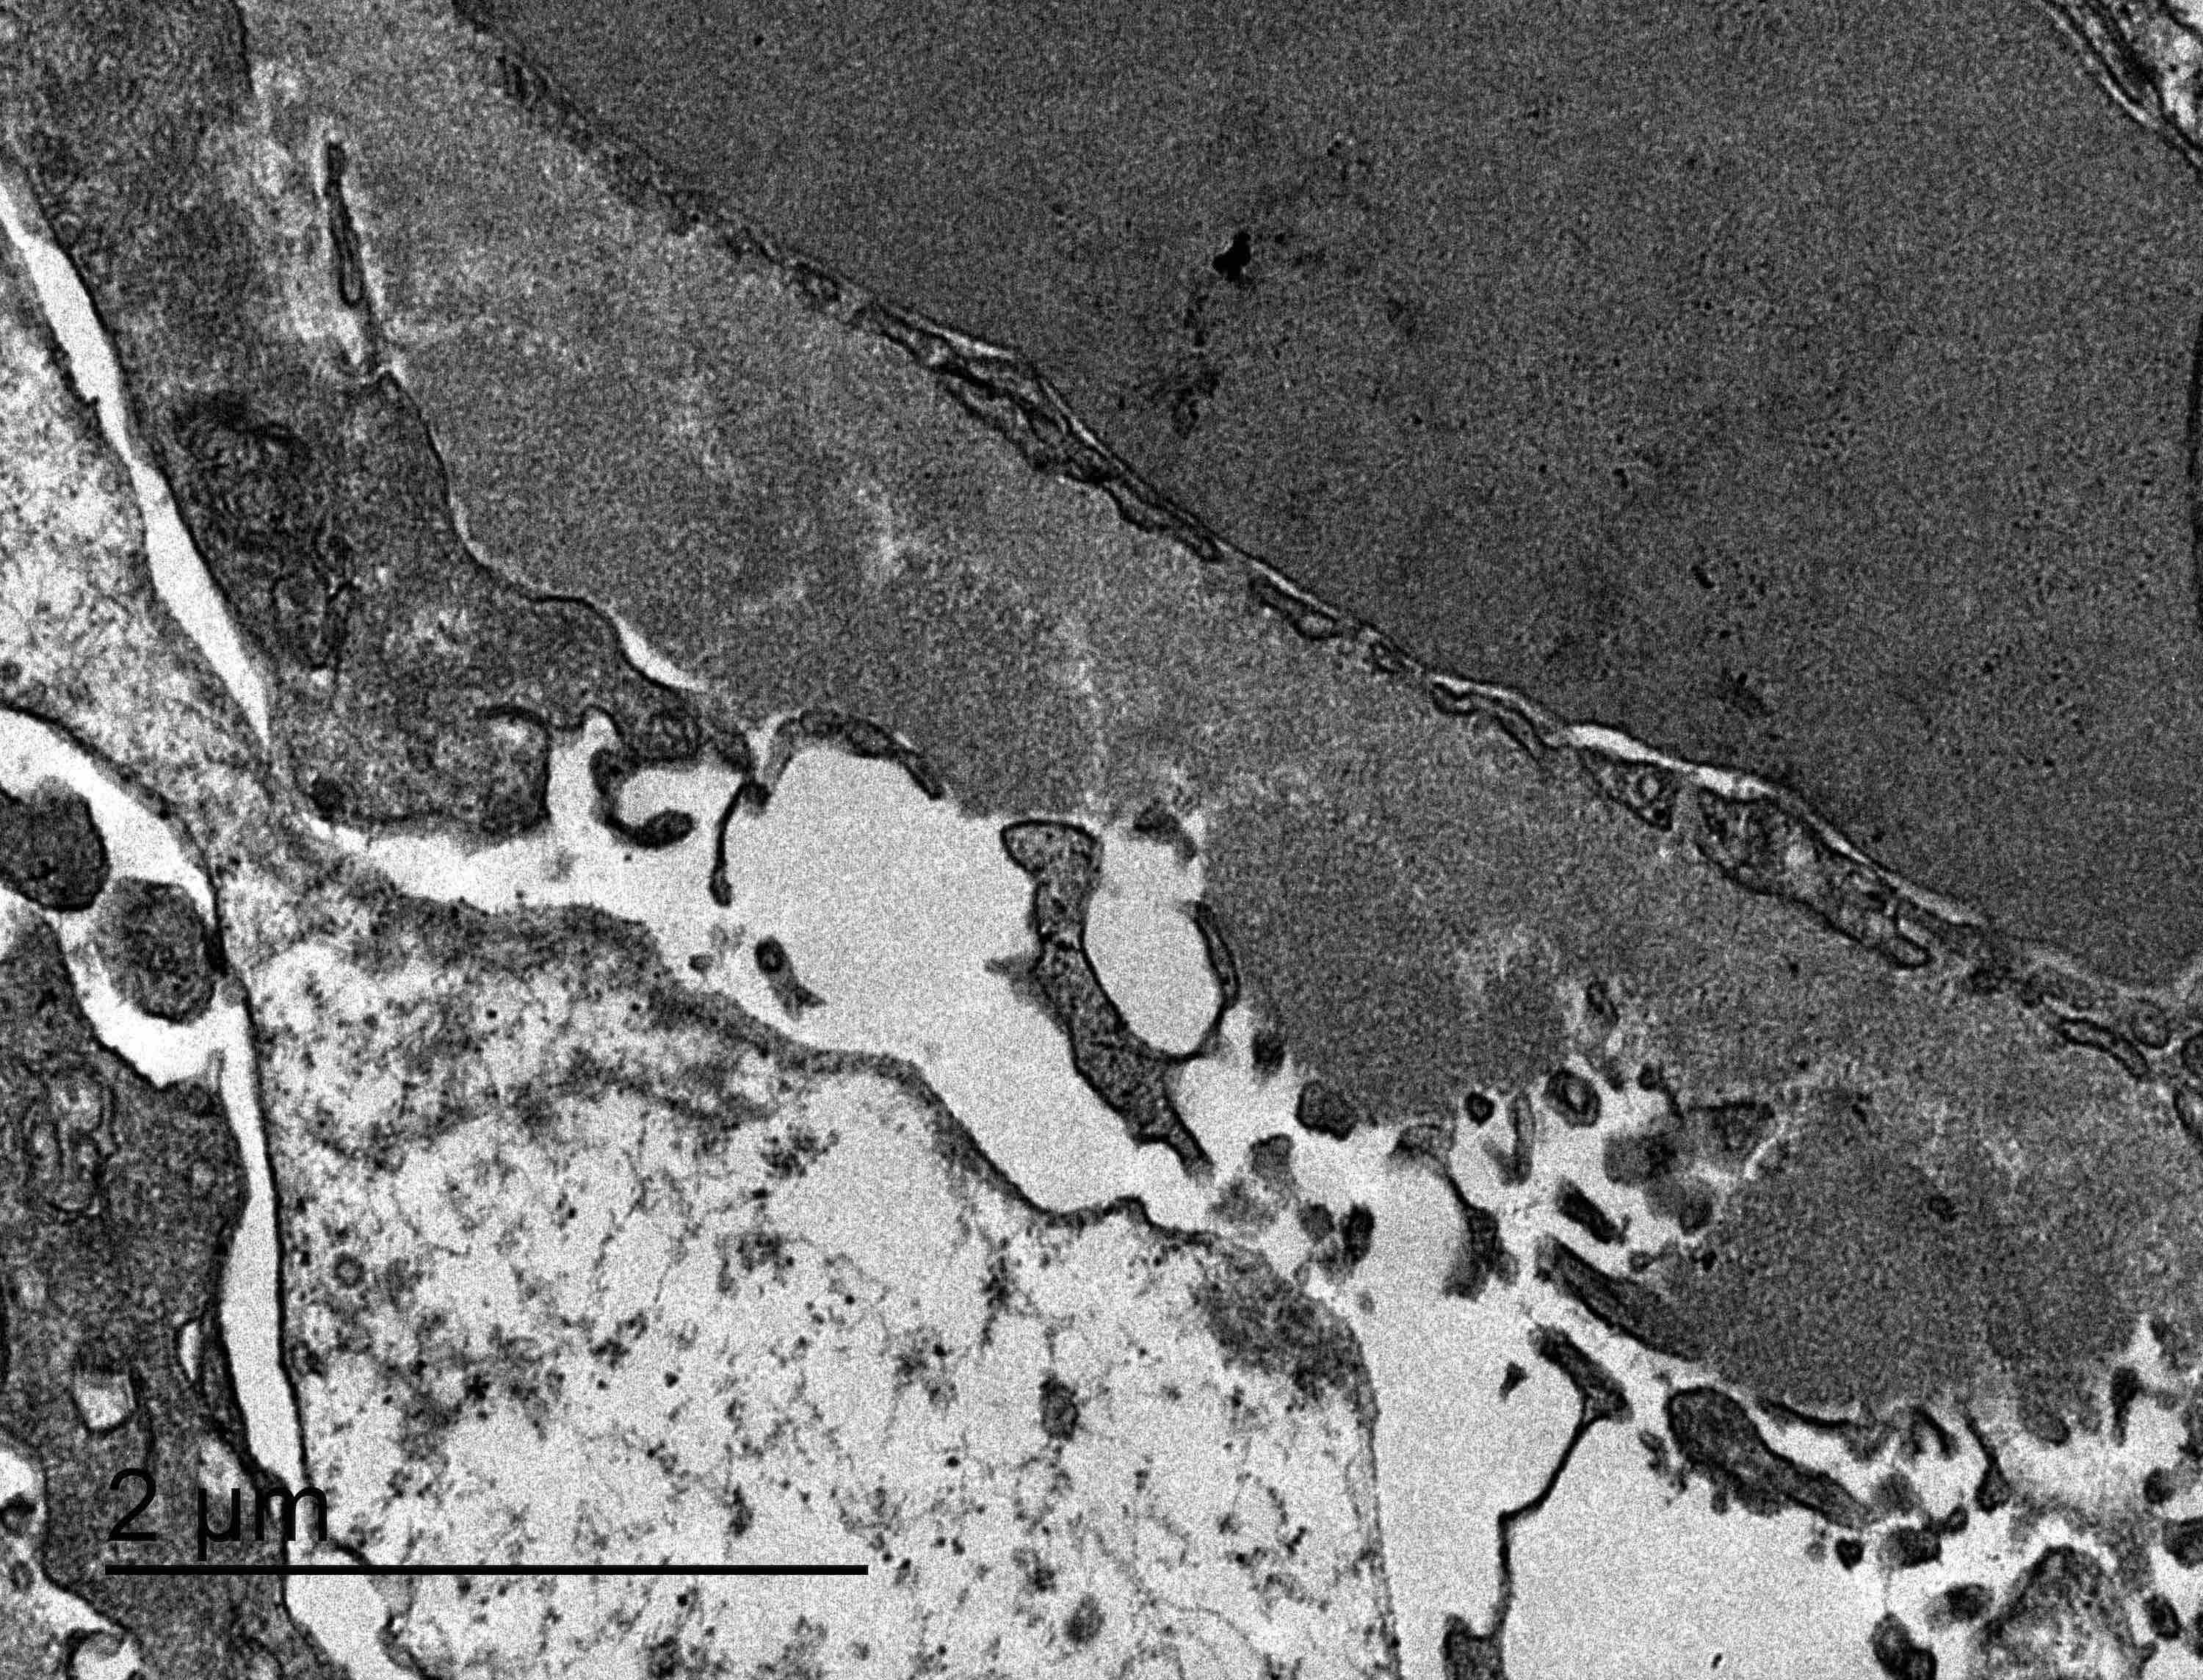

Electron microscopy description

- Electron microscopy confirms the subepithelial localization of electron dense deposits

- 4 stages:

- Scattered electron dense deposits on the epithelial side of the glomerular basement membrane

- Subepithelial deposits with basement membrane material (spikes) between deposits

- Subepithelial (or intramembranous) deposits with basement membrane material between and surrounding deposits

- Electron lucent areas represent probable resorption of prior subepithelial immune complexes

- References: Colvin: Diagnostic Pathology - Kidney Diseases, 2nd Edition, 2015, Zhou: Silva's Diagnostic Renal Pathology, 2nd Edition, 2017

Electron microscopy images

Contributed by Ana Belén Larqué, M.D., Ph.D. and Jonathan E. Zuckerman, M.D., Ph.D.